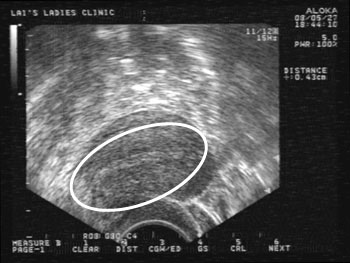

EM子宮內膜刺激術根據國外一份研究,懷孕率高達百分之一百,真的還是假的? http://www.flickr.com/photos/41541241@N08/7649010462/sizes/c/in/photostream/ http://www.flickr.com/...